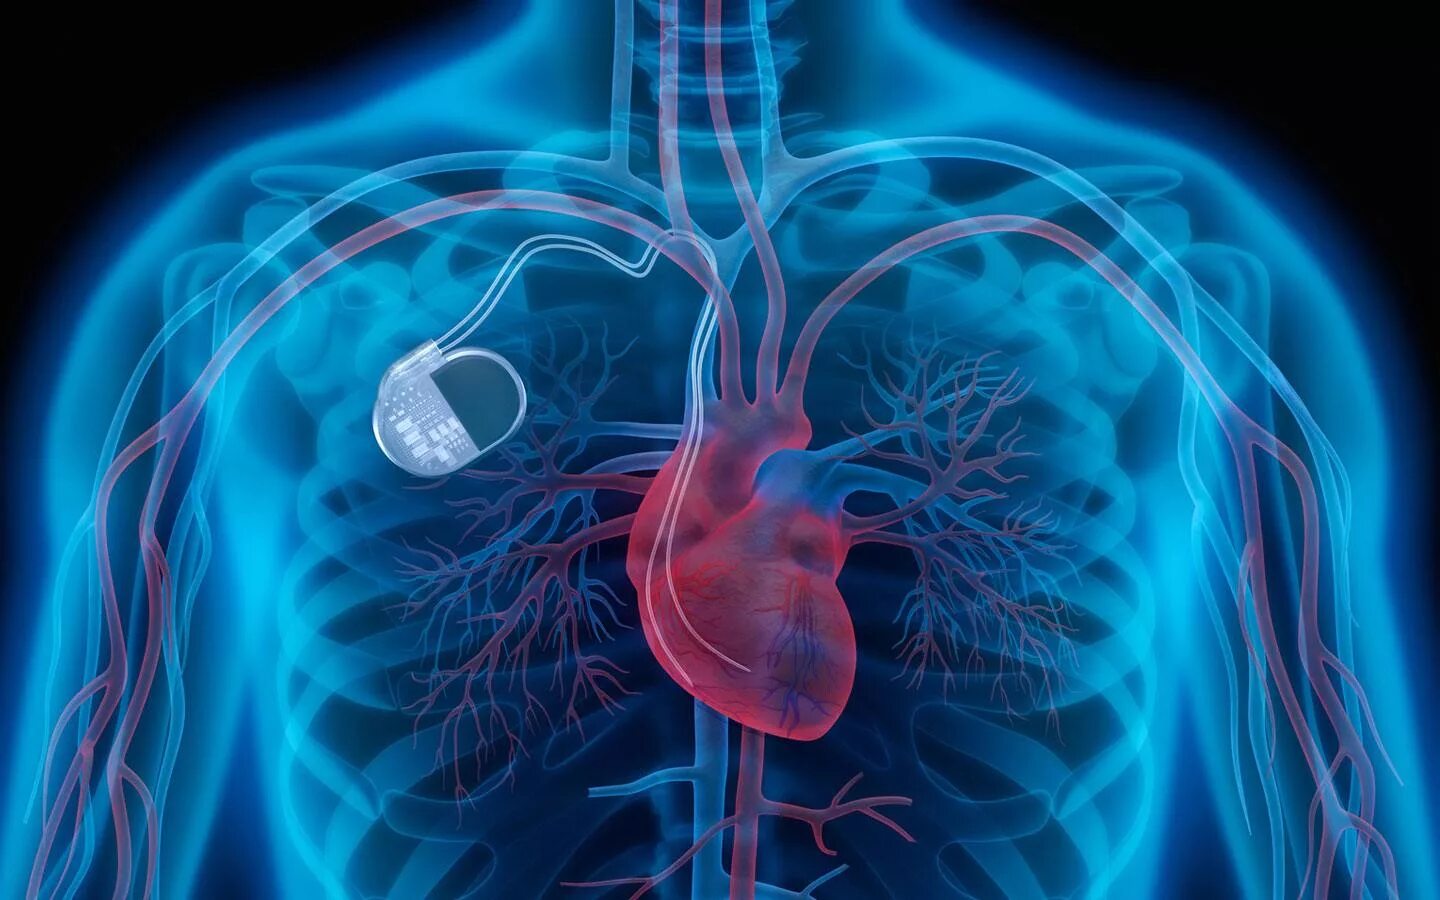

Как делают операцию кардиостимулятор